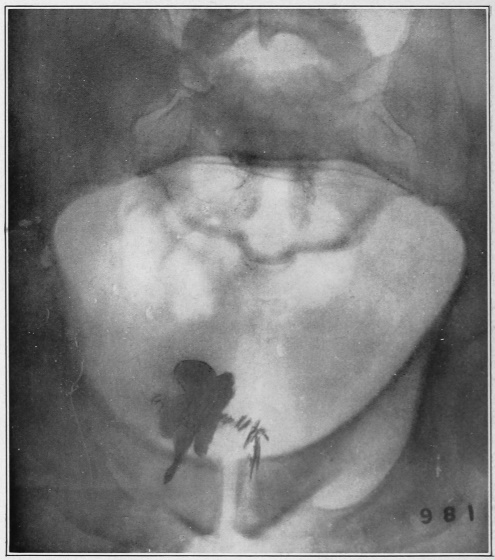

Nine Radiograph Illustrations Showing Mucus Channels and Cavities200

CHAPTER XXV.

Chronic Mucous Proctitis and Sigmoiditis—Usually Diagnosed as Chronic Mucous Colitis202